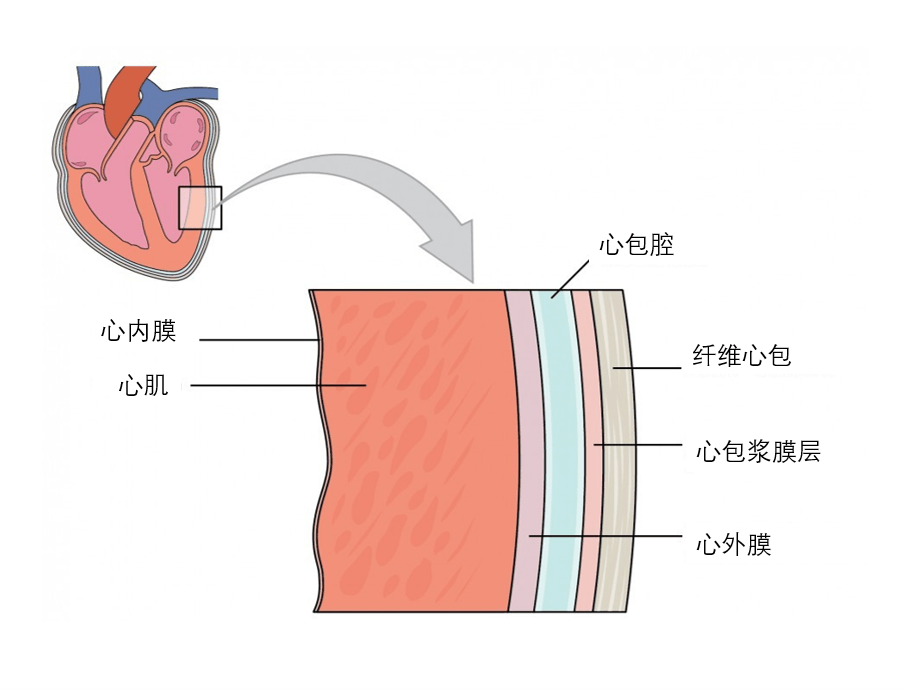

心脏被心包包围,心包是一个三层囊状结构,保护心脏免受外部创伤和感染。 纤维心包是坚韧的最外层。 纤维心包附着在横膈膜和胸骨上,通过防止过度运动和过度拉伸来稳定心脏。心外膜是心包的最内层。它与心肌(心脏的中间肌肉层)相邻。心包腔位于心外膜和心包之间。其中充满了润滑性浆液,可减少心脏收缩时的摩擦。